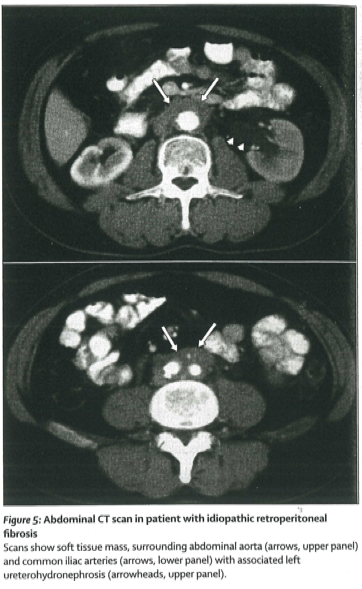

Vagilo等はランセット論文5)の下記図5で、血管に造影剤を点滴した腹部CT画像典型例を上と下の図で説明しています。上下の図の下部の(白い)脊椎の前に造影された(丸い)血管が白く映っていて、二本の白矢印で指摘された肥厚が、後腹膜線維症の病変に相当します。上図は腹部大動脈、下図は左右の大腿動脈に分離した部分の、腹部CT像となります

図5 上・下 (Vagilo5)から引用)

図5